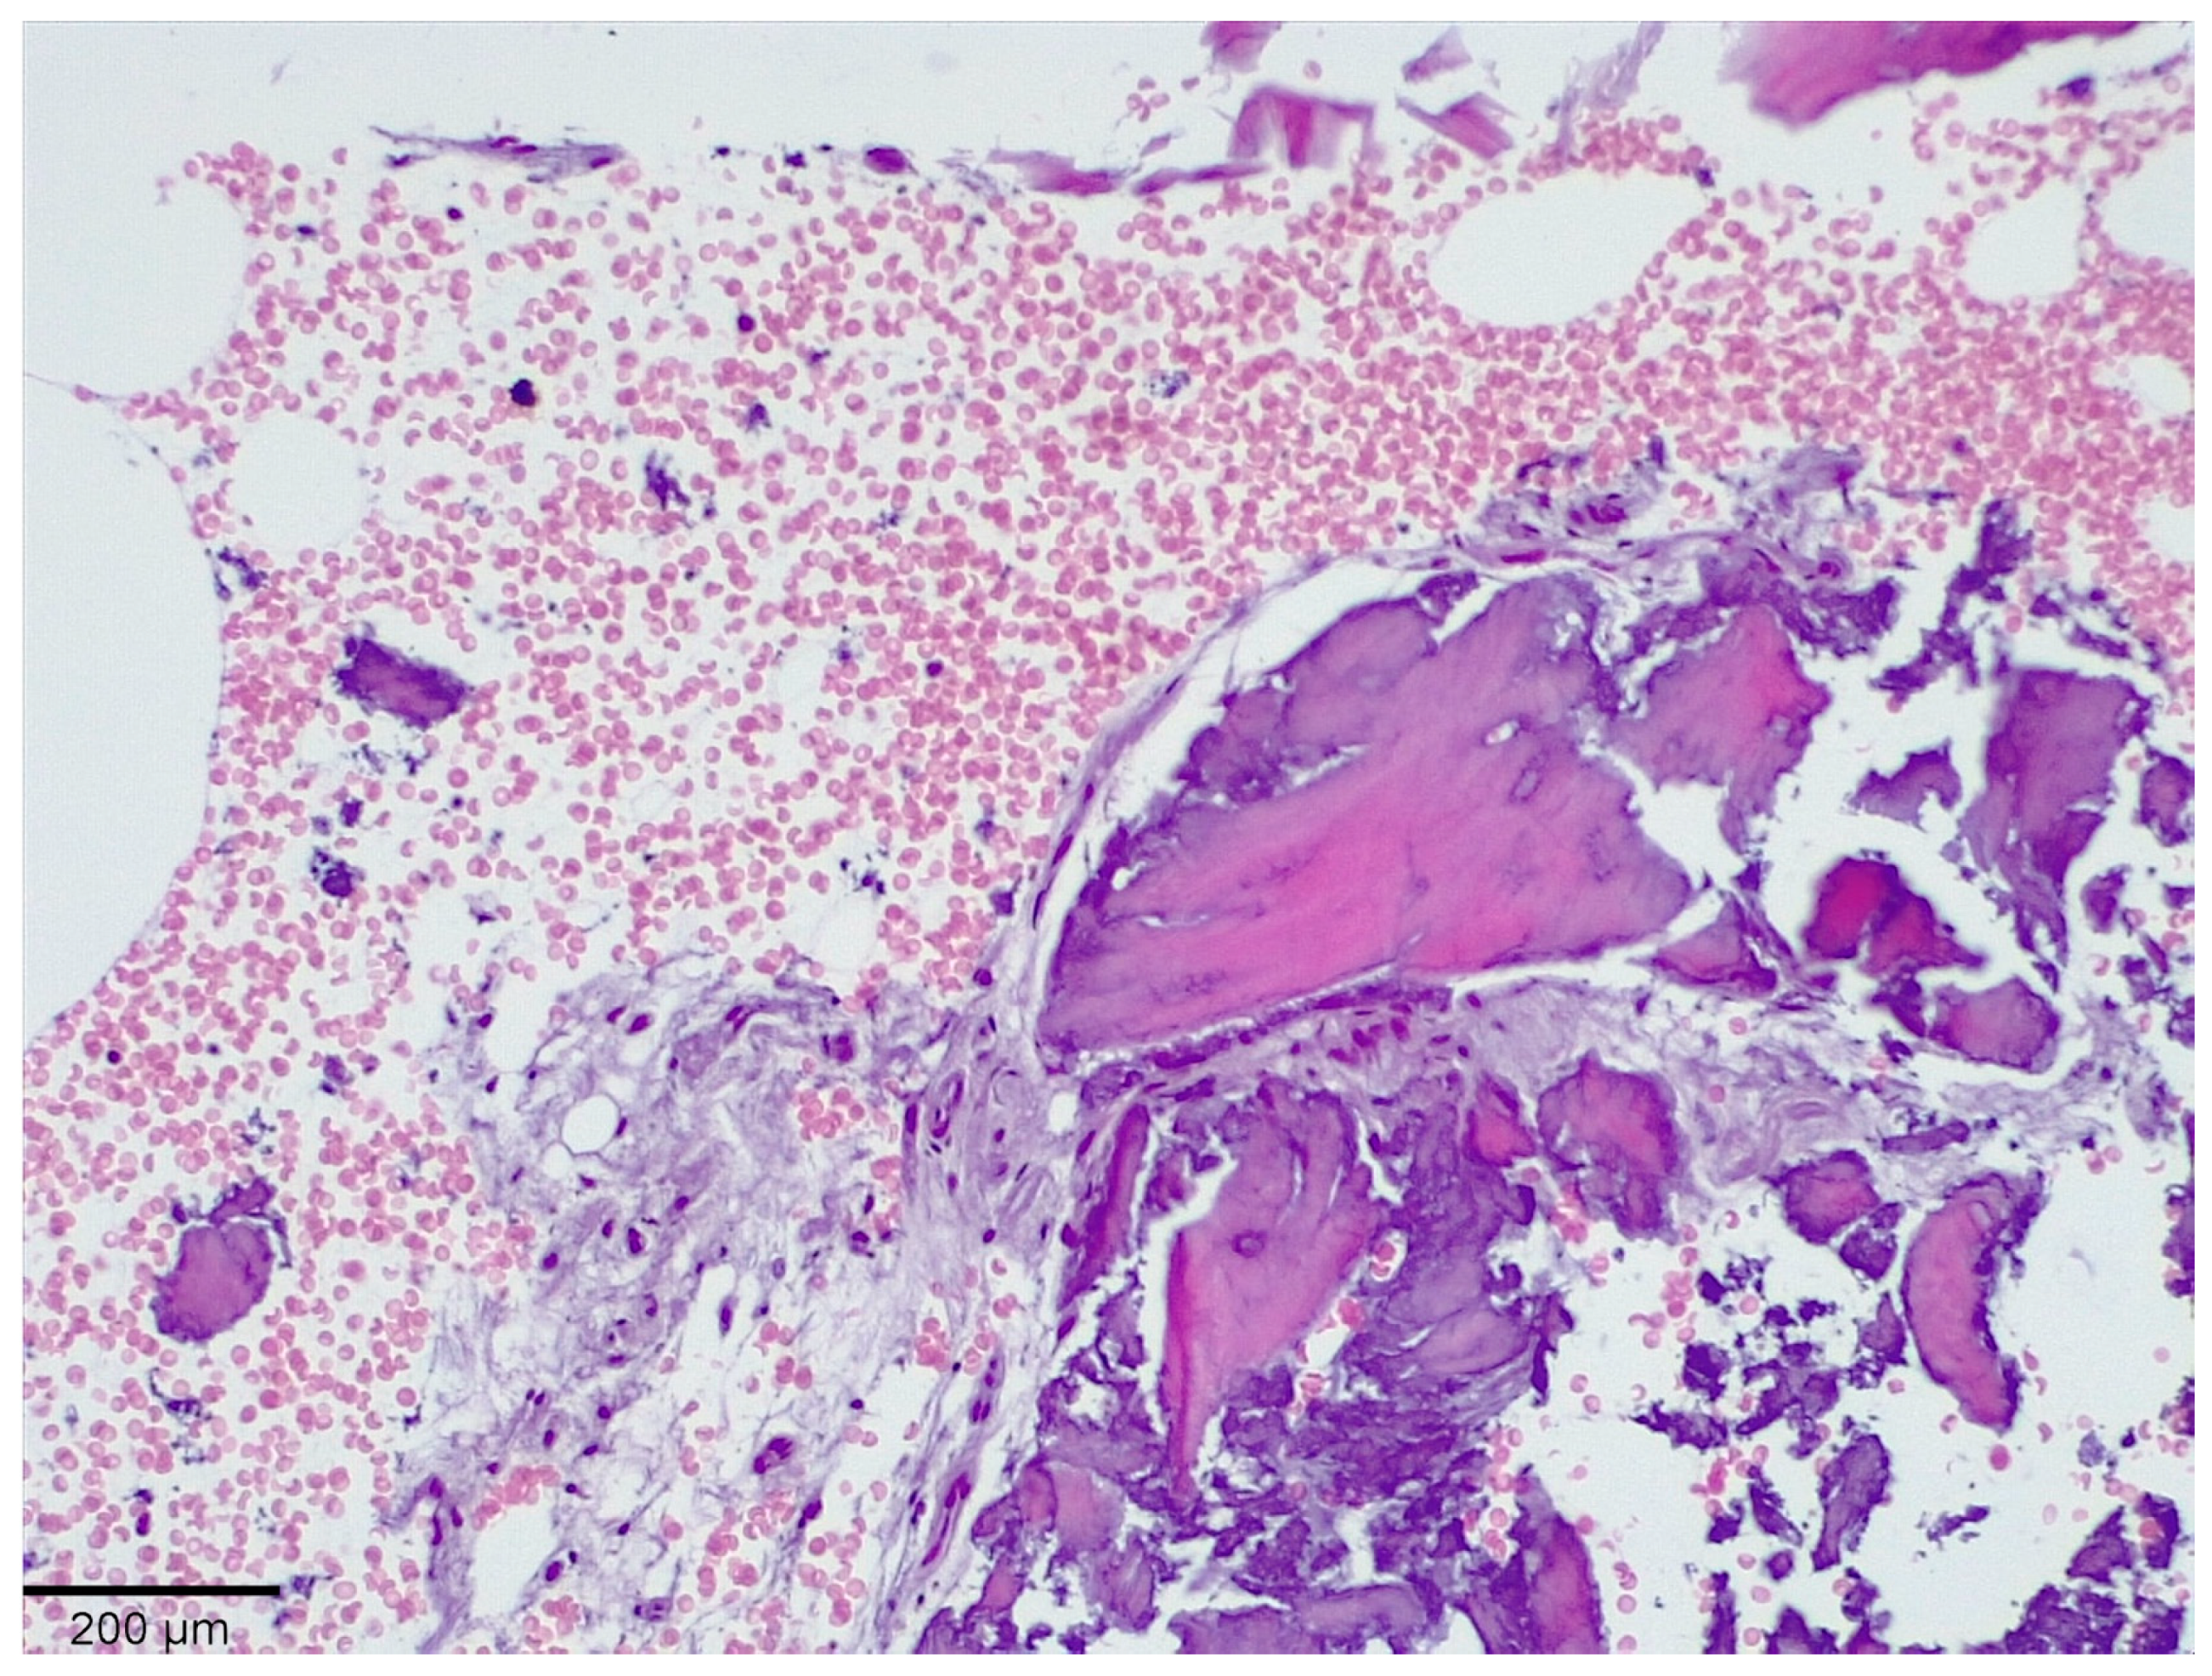

3.1. Histological Analysis Showed Signs of New Bone Formation at 60 Days

3.2. Histologic Data Obtained after Samples Analysis at 24 Months of Evaluation